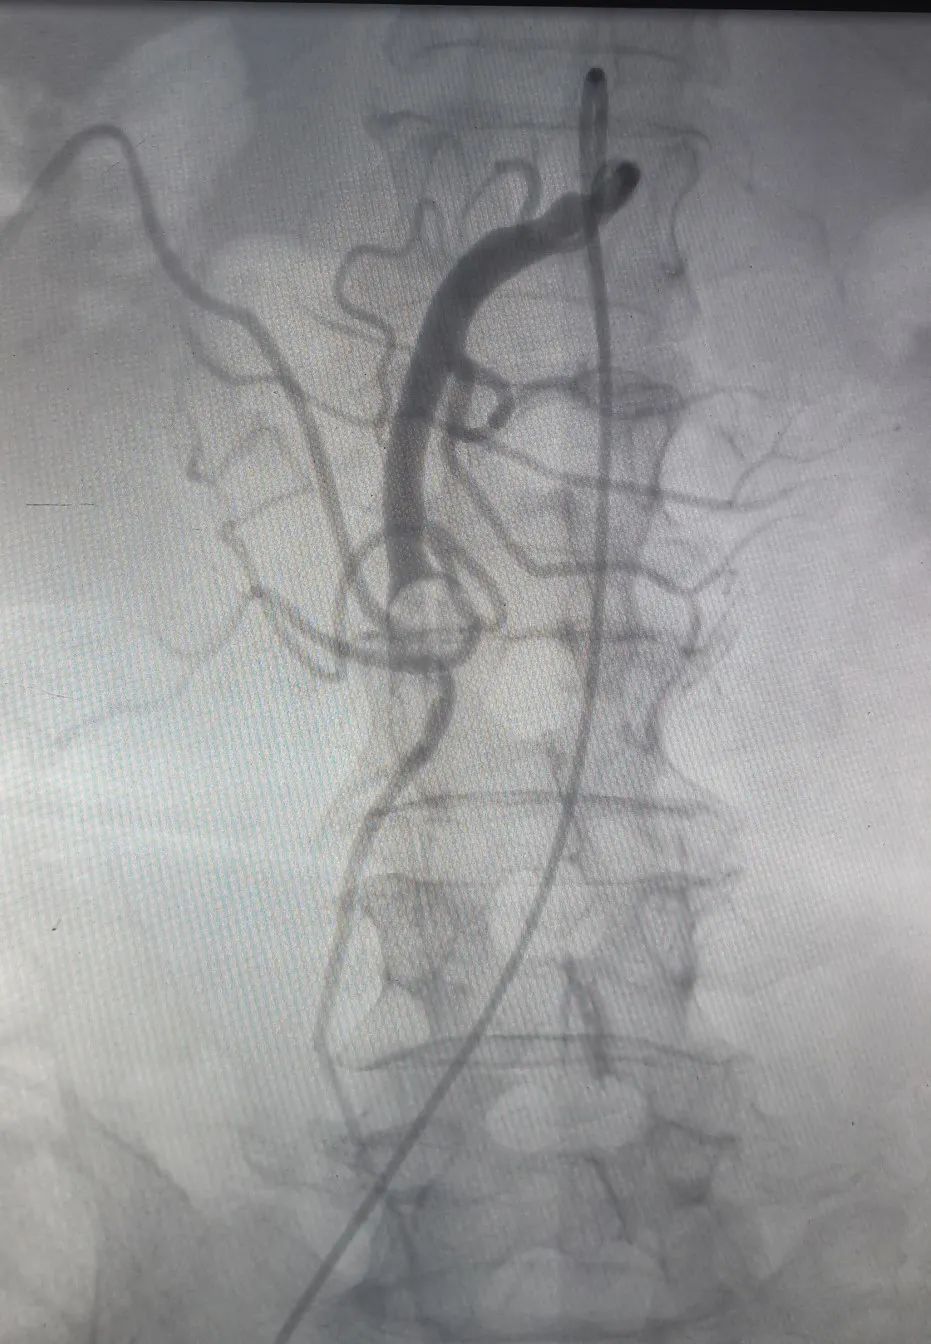

血栓介入治疗:除了常规抗凝治疗,动脉血栓、深静脉血栓开展导管溶栓、机械吸栓术,肺栓塞碎栓术、下腔静脉滤器置入、狭窄静脉支架置入等周围血管疾病的腔内治疗。

▲肠系膜上动脉栓塞吸栓术前后对比